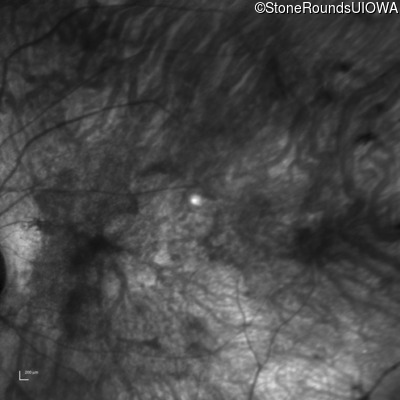

Infrared Fundus Photograph - Right - 20/200 +2

Exemplar